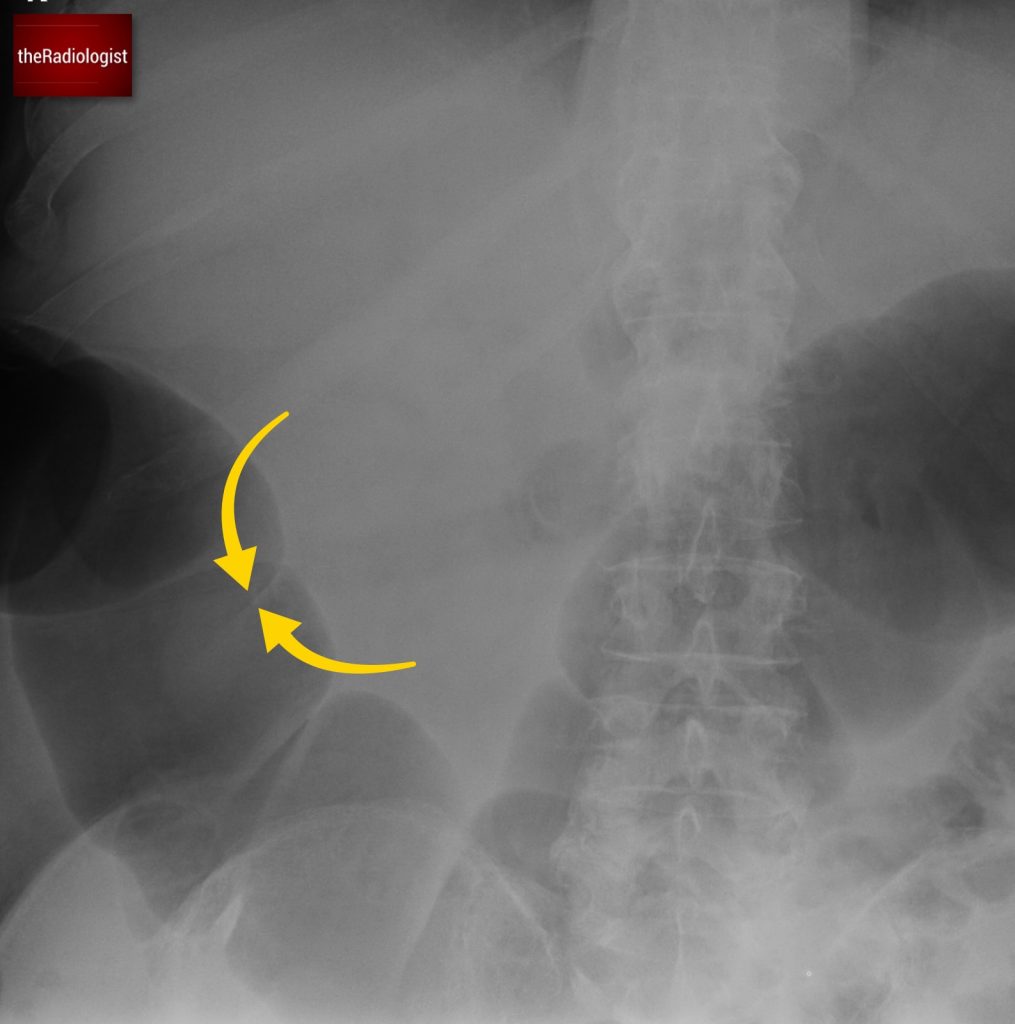

If we look at the psoas muscles on this scan below we can see there is some asymmetry . The right psoas is larger than the left and we’ve lost some of the fat planes within the muscle.

Compare the psoas muscles side by side. The right sided psoas muscle appears expanded with a loss of its normal fat planes.

Also as we scroll down we can see there is fat stranding surrounding the psoas muscle extending into the pelvis.

There is fat stranding surrounding the psoas extending into the pelvis.